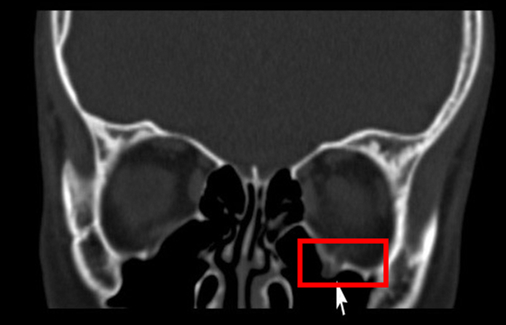

眼眶骨折常见的ct表现